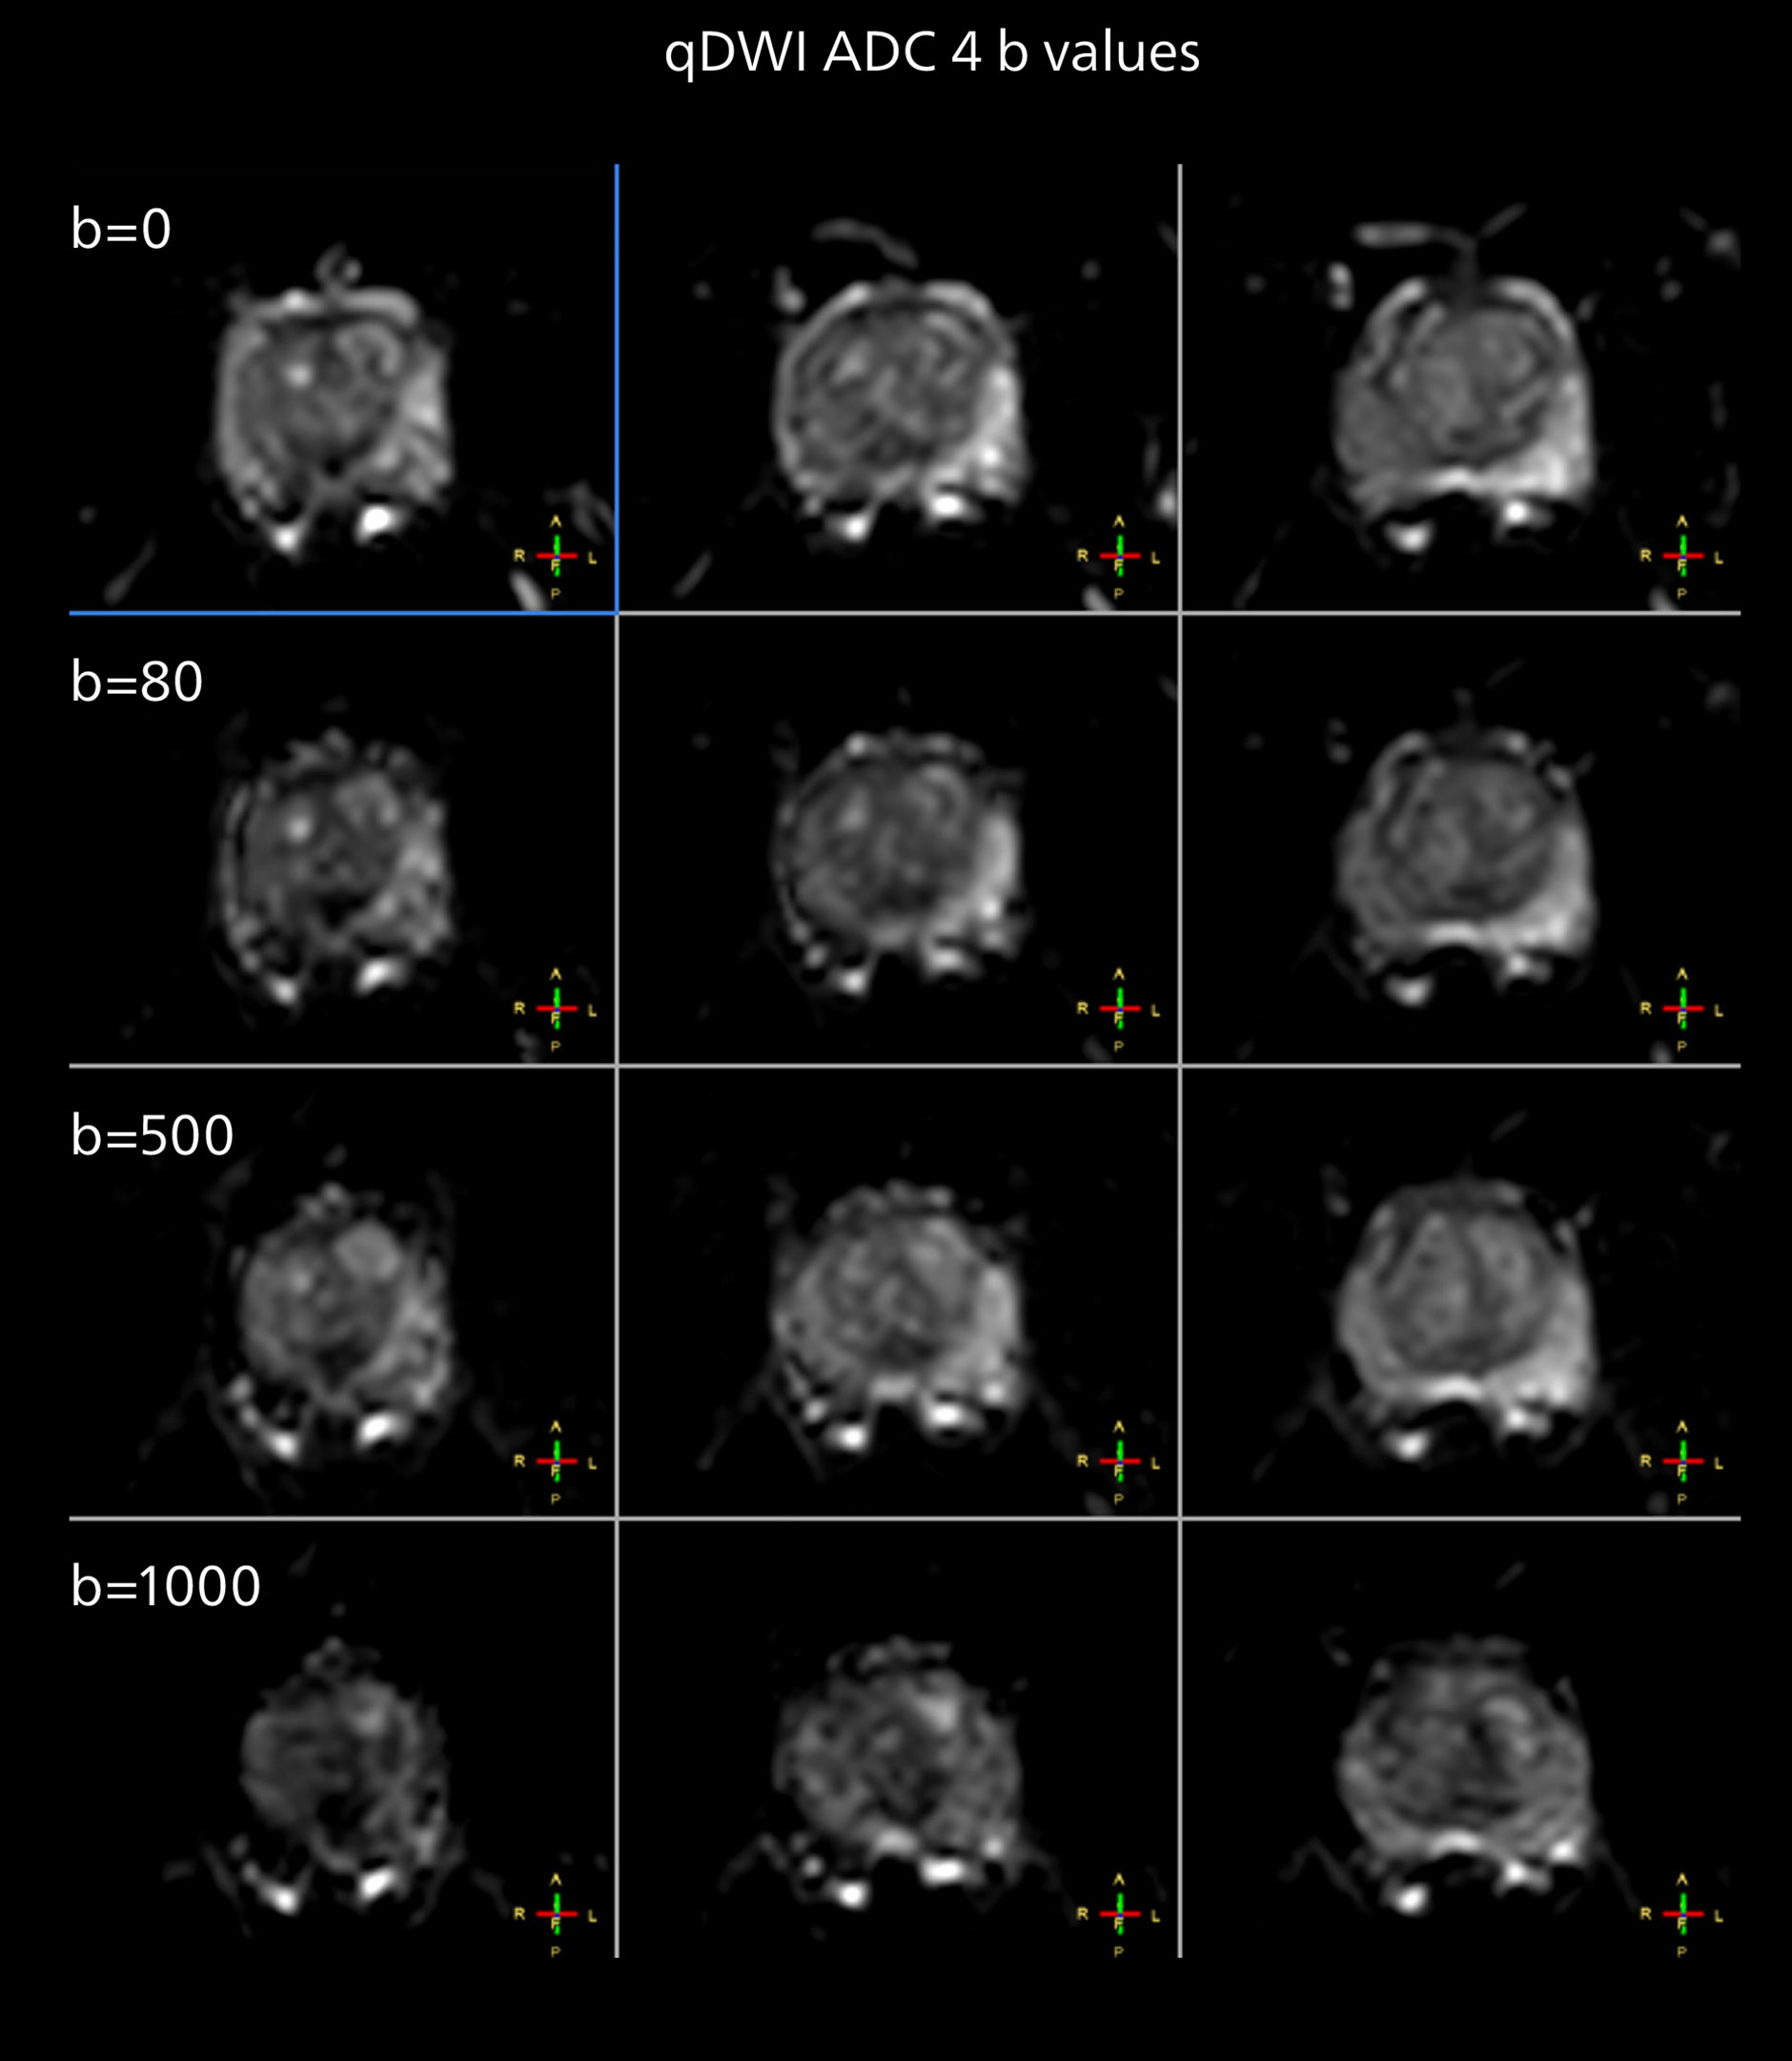

The examples on the left show the regular clinical diffusion protocol with four b-values up to b1000 s/mm². On the right, the T2W image shows a hypointense lesion that has low ADC and is clearly visible in b1400 and b2000 diffusion images, suggesting malignancy.